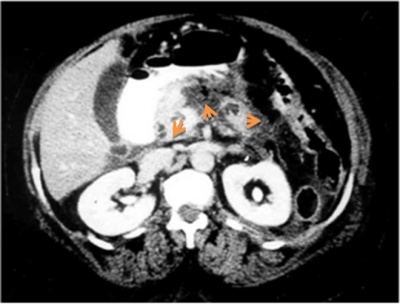

האבחנה נקבעת באמצעות העל-שמע (אולטרה-סאונד) והטומוגרפיה הממוחשבת המדגימים גוש כיסתי (ציסטי) המכיל תוכן סמיך ואוויר (תצלום 5.9).